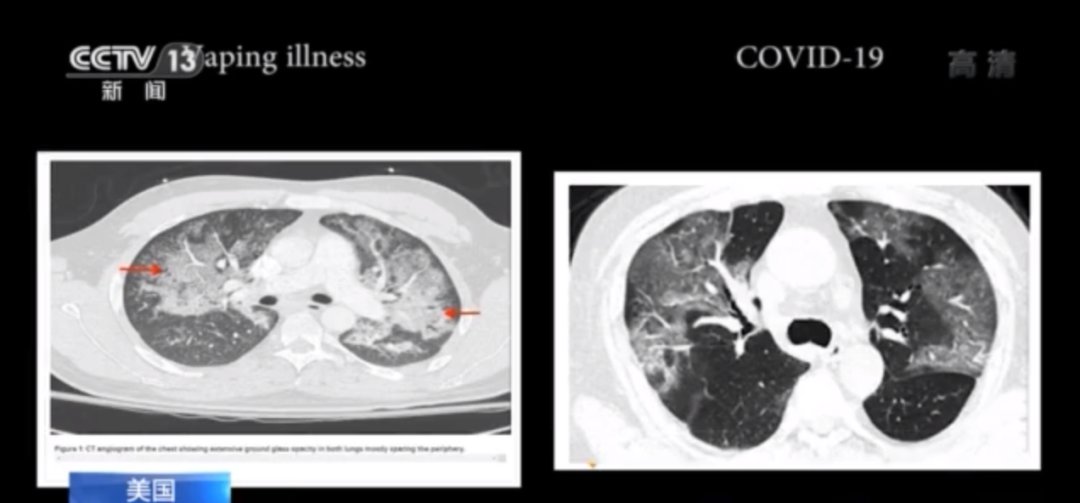

美国电子烟肺炎与新冠肺炎症状几乎无异

其病症与新冠肺炎症状几乎没有差别,且致病原因未知。

时间上的巧合和肺部CT的相似让人们不禁联想到所谓“电子烟肺炎”和新冠肺炎之间的关系。有网友称,